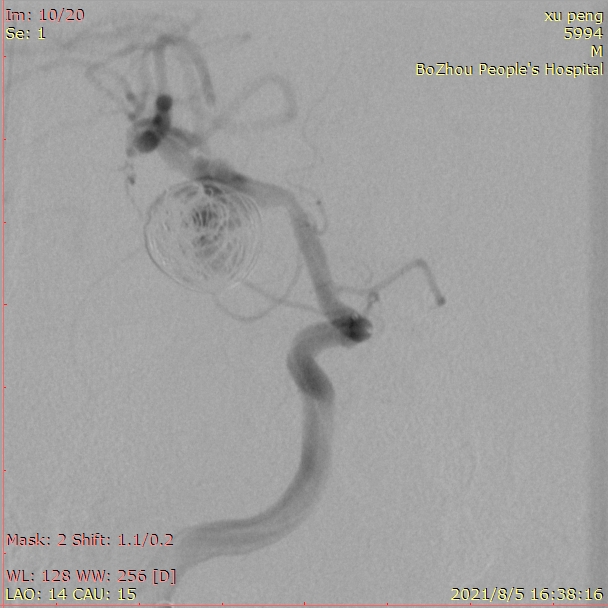

成篮圈的即刻造影和蒙片

依次填入14/30、13/30、11/30、10/20*2弹簧圈后,发现第一根微导管已经基本固定在瘤颈上方,而瘤体中心及下方仍显影明显。这时我们暂不撤回第一根微导管,然后将第二根SL-10微导管塑形后送入瘤内下方继续填圈。

用两根微导管依次缓慢、小心填入9/30,8/30,7/20,6/20,5/10,3/8等圈,即刻造影,动脉瘤不显影,最终达到完全栓塞。

观察15分钟后再次造影,正位片。

观察15分钟后再次造影,侧位片。

载瘤动脉通畅,手术结束。